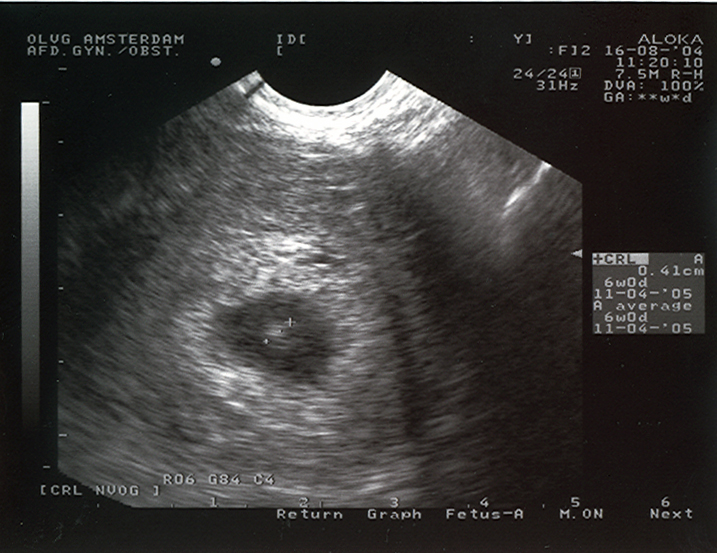

Ultrasound picture of a 4-week old pregnancy. On the right you can read the size: 0,41 cm. This means that the mother is about 12 days over time. If a pregnancy like this is unwanted, we can end it on our ship when outside the 12 mile zone.

copyright 2004 Women on Waves.